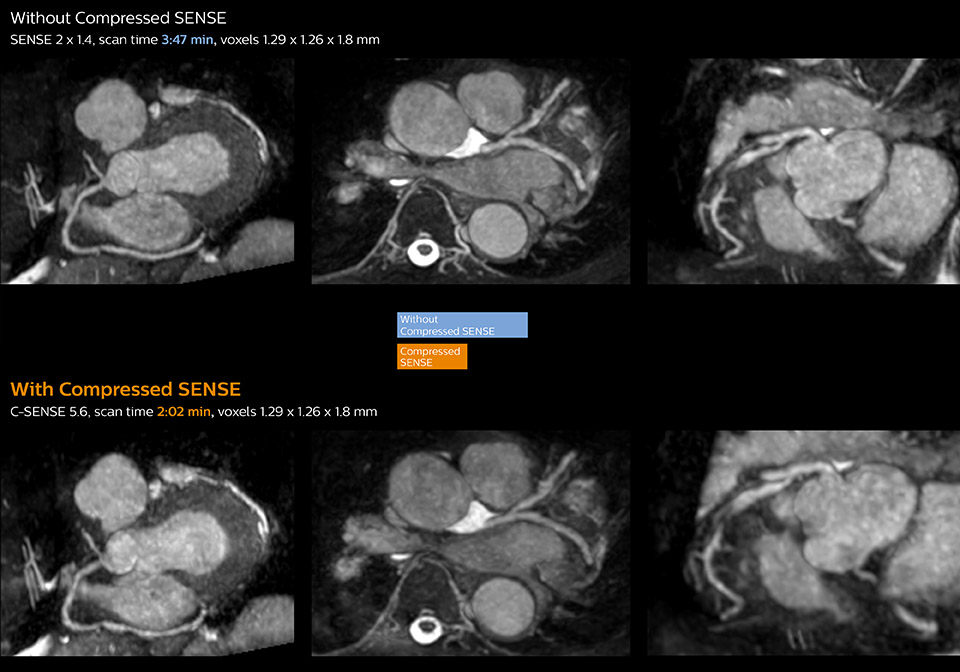

Cardiac MRI of acute myocardial infarction (AMI) w/wo Compressed SENSE

These images of a patient with acute myocardial infarction images were acquired on Ingenia 1.5T with and without Compressed SENSE.

Dr. Koshi Miyake, cardiologist, explains that scanning of patients with cardiac arrhythmia can be challenging, as scanning times can become very long due to the varying heart rate. So his most important motive to implement Compressed SENSE in cardiac MRI exams was to reduce the burden of breath holds for the patient, while maintaining high image quality. He hopes this can also help to reduce motion caused by the difficulty for patients to hold their breath.

“Compressed SENSE has now been implemented in all cardiac exams. Thanks to the acceleration, fewer breath holds are now needed, or breath hold times are shortened. This reduces the burden of the exam for cardiac patients, without affecting the quality of information required for cardiac function analyses,” he says. “Because it’s easier for patients to comply with the breath hold times”

“In our previous cardiac cine sequence, we were acquiring two slices during one breath hold. With Compressed SENSE, we increased this to four slices per breath hold. It is also possible to shorten scanning time using a C-SENSE factor 6 without sacrificing image quality.”

“Typically, in scans with high contrast, such as 2D balanced TFE cine, a quite high C-SENSE factor may be used. When we tried a higher C-SENSE factor, we saw still no significant influence on cardiac ejection fraction, but 2D image quality started to decline. For coronary imaging, we use a C-SENSE factor of 3 in 3D balanced TFE, or even up to 4 when contrast is high.”